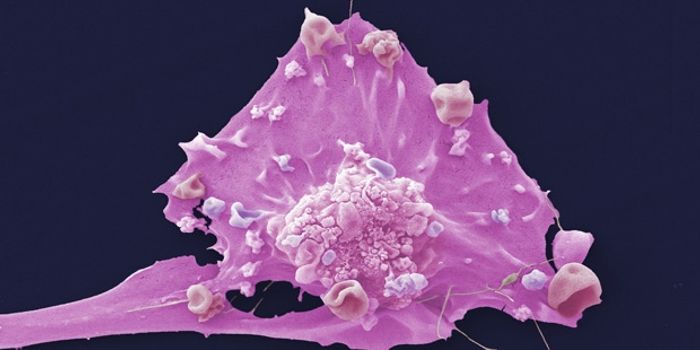

Cancer

Stay informed on development in cancer and oncology diagnosis, prevention and treatment. As the race toward a cure for cancer continues, advances in cancer research are constantly revealed as innovation in the field of oncology progresses.

MAR 18, 2015CancerCancer stem cells often cause tumors to form and are particularly difficult to destroy. They resist chemotherapy, allowi ...

APR 17, 2016CancerVirtually every type of cancer has metastatic potential – that is, the tumor cells can leave its original site and ...

FEB 20, 2017CancerResearchers have captured how a new organo-metal compound infiltrates cancer cells and destroys its most vulnerable orga ...